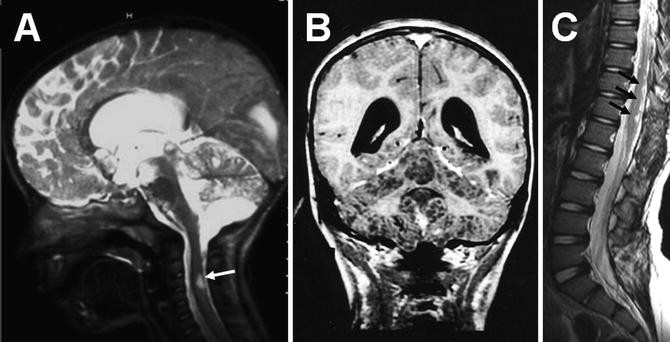

Diffuse leptomeningeal disseminated glioneuronal tumor DL-GNT is a rare brain tumor that presents as a plaque-like subarachnoid tumor commonly involving the basal cisterns and interhemispheric fissure of children but lacking intraparenchymal tumor. Report of three cases and review of literature Pediatric Hematology and Oncology 1010800888001820191711270 1-11 2020. Primary diffuse leptomeningeal glioneuronal tumors of the central nervous system. Diffuse leptomeningeal glioneuronal tumor DLGNT has been recently described in the literature. In an endemic region diffuse leptomeningeal enhancement on neuroimaging with associated communicating hydrocephalus is usually suggestive of infective. Diffuse leptomeningeal disseminated glioneuronal tumor DL-GNT is a rare brain tumor that presents as a plaque-like subarachnoid tumor commonly involving the basal cisterns and interhemispheric fissure of children but lacking intraparenchymal tumor.

A radiological hallmark of this disease is widespread leptomeningeal enhancement that may involve the. Diffuse leptomeningeal glioneuronal tumor DL-GNT is a new entity described in the 2016 World Health Organization WHO classification of brain tumors. 4 Abongwa C Cotter J Tamrazi B Dhall G Davidson T Margol A. Diffuse leptomeningeal disseminated glioneuronal tumor DL-GNT is a rare brain tumor that presents as a plaque-like subarachnoid tumor commonly involving the basal cisterns and interhemispheric fissure of children but lacking intraparenchymal tumor. Histologically the tumors are composed of sheets of monotonous. Diffuse leptomeningeal glioneuronal tumor DL-GNT is a rare brain tumor that presents as a plaque-like subarachnoid tumor commonly involving the basal cisterns and interhemispheric fissure of children but lacking intraparenchymal tumor.